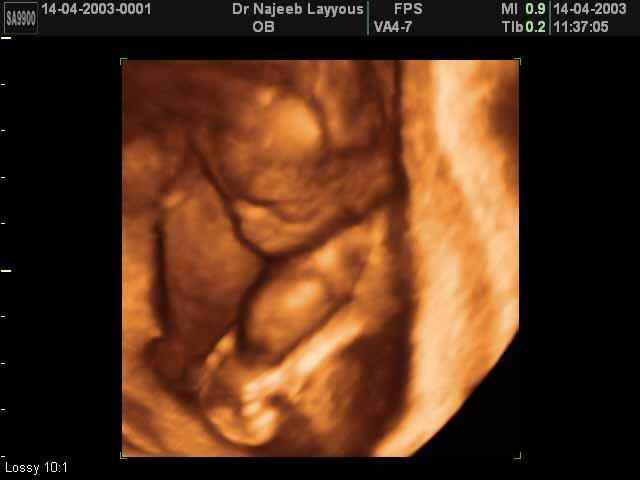

- تصرفات الجنين داخل الرحم

- صور لأطراف الجنين

- صور لتصرفات الجنين داخل الرحم

صور لتصرفات الجنين داخل الرحم بجهاز الالتراساوند ثلاثي الأبعاد | الدكتور نجيب ليوس